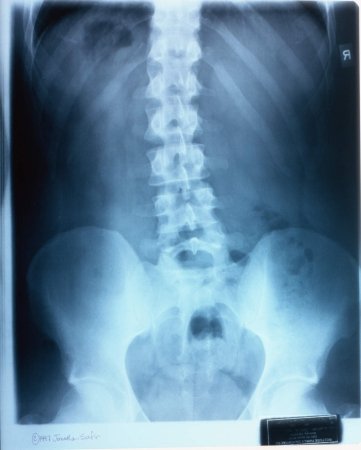

Костоправ Олександра Октисюк із Ратнівщини лікує людей без історій хвороб і рентгенівських знімків.

Жінка лікує защемлення нервів, остеохондрози і сколіози, справляється зі свіжими й задавненими переломами та вивихами, допомагає при ДЦП.